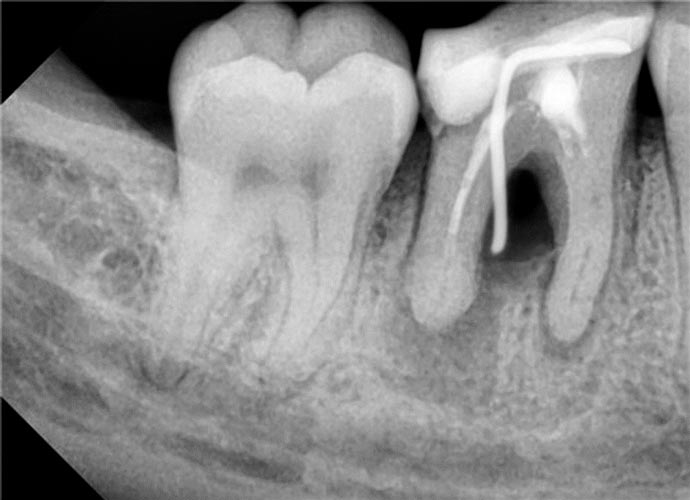

Перфорації кореневого каналу

• клініка

• діагностика

• менеджмент

Перфорації корня каналу

Класифікація перфорацій. Вплив розташування на прогноз і тактику.

Вибір матеріалу в залежності від розташування і розміру перфорації( фуркаційна, середньої третини і апікальна)

Чи є найкращий матеріал для закриття перфорації?

Правила використання композиту для закриття перфорації.

Використання біокерамічних силерів, переваги і недоліки

Сучасний «золотий стандарт» МТА? Чому МТА може не застигати? Робота з перфорацією один чи два візити? Вплив на прогноз. Відеодемонстрація роботи з різними матеріалами і різною локацією. Допоміжне обладнання при роботі з мікроскопом і без. Прогноз закриття перфорацій. Розгляд клінічних питань слухачів щодо перфорацій( підготувати клінічні ситуації). Вебінар надає 1 бал БПР,